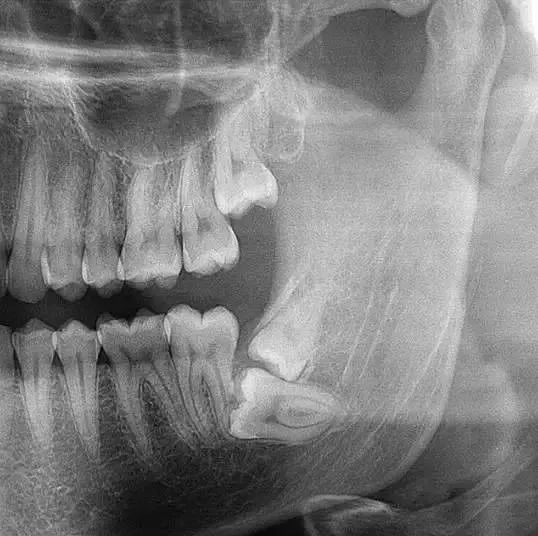

◆智齿拔除

智齿,一般长在牙槽骨里,有的正常萌出,有的埋伏在牙槽骨里部分萌出或完全没有萌出。所以,拔除智齿需要拍全景片,医生才能看清楚牙齿长势、牙根位置以及和面部神经的距离!